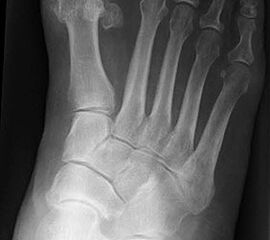

Konventionelles Röntgen

Stehende konventionelle Röntgenbilder eines Fußes mit Planovalgus Deformität Stadium II b dorsoplantar (dp) und seitlich. Auf der dp-Aufnahme zeigt sich die talo-calcaneare Divergenz, der gegenüber dem Kalkaneus nach anterior gleitende Talus und d

Stehende Aufnahmen des Fußes dorsoplantar (dp) und seitlich sowie des OSG anteroposterior (ap) sind die Grundlage der konventionellen Röntgendiagnostik (Abb. 5). Ergänzend werden gelegentlich die Rückfuβ-Alignement Aufnahme nach Saltzman 19 und Vergleichsaufnahmen der Gegenseite durchgeführt.

Der Talo-Metatarsale I Winkel bzw. die laterale talonaviculare Subluxation auf der stehenden dorsoplantaren Aufnahme des Fuβes dokumentieren das Ausmaβ des Vorfuβ abductus (Abb. 6 a,b). Ein dp Talo-Metatarsale I Winkel von > 10° (nach medial konvex) ist als pathologisch anzusehen. Mit der Bestimmung der talocalcanearen Divergenz (Abb. 6 c) erhält man ein Eindruck über das Ausmaβ des Rückfuβ valgus; eine leichte Divergenz bis ca. 12° gilt als physiologisch 20.